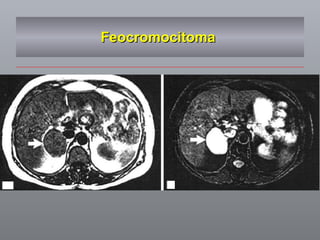

Feocromocitoma

FEOCROMOCITOMA Clínica % Hipertensão  82 Cefaléia  49 Palpitações  40 Sudorese  37 Tremor / agitação / ansiedade Catecolaminas Goldstein RE, et al.  Clinical Experience Over 48 years with feocromocytoma Ann surg 1999; 229(6) 755-764

FEOCROMOCITOMA Clínica %Hipertensão 82 Cefaléia 49 Palpitações 40 Sudorese 37 Tremor / agitação / ansiedade Catecolaminas Goldstein RE, et al. Clinical Experience Over 48 years with feocromocytoma Ann surg 1999; 229(6) 755-764